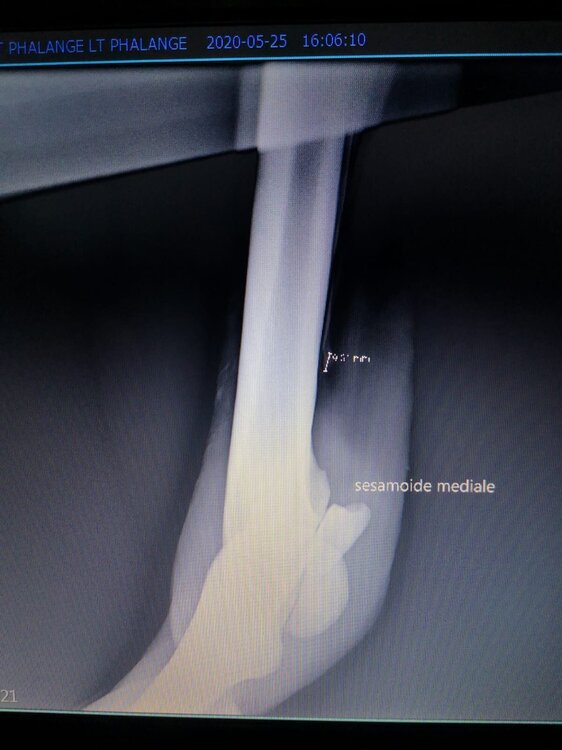

Salve volevo chiedervi qualche informazione in merce tò a un problema che ho avuto con la mia puledra. Qualche settimana fa mentre stavo lavorando alla corda è scivolata urtato l'arto posteriore sinistro. Arrivati in box ho messo dell'acqua a pressione perché si era gonfiato sia il nodello sia il pastorale. Già l'indomani l'arto era sgonfio ritornato normale, quindi ho continuato a lavorarla. Ma dopo qualche giorno di lavoro alla corda leggerissimo, al rientro in box ho notato che sia il nodello che il posturale gonfiavano nuovamente. Allora ho chiamato il veterinario che ha detto che la cavalla aveva una lussazione e mi ha insegnato come cura una fasciatura con della creta per 24h per cinque giorni e un antinfiammatorio. Dopo un paio di giorni la fasciatura ha fatto come delle vesciche e il gonfiore è aumentato dal pastorale alla garra. Abbiamo chiamato un altro veterinario abbiamo fatto vedere anche a lui la cavalla e diceva che poteva essere la frattura del ditino, ma si dovevano fare le lastre per essere sicuri. Ora abbiamo fatto le lastre e il radiologo dice che c'è dell'infiammazione ma non c'è niente di grave. Il veterinario,viste le lastre dice che deve essere operata. Allora abbiamo consultato un'altro veterinario che dice che la cavalla non ha assolutamente niente. Ora io vi allego le radiografie, datemi un vostro parere perché non só più cosa fare. Grazie